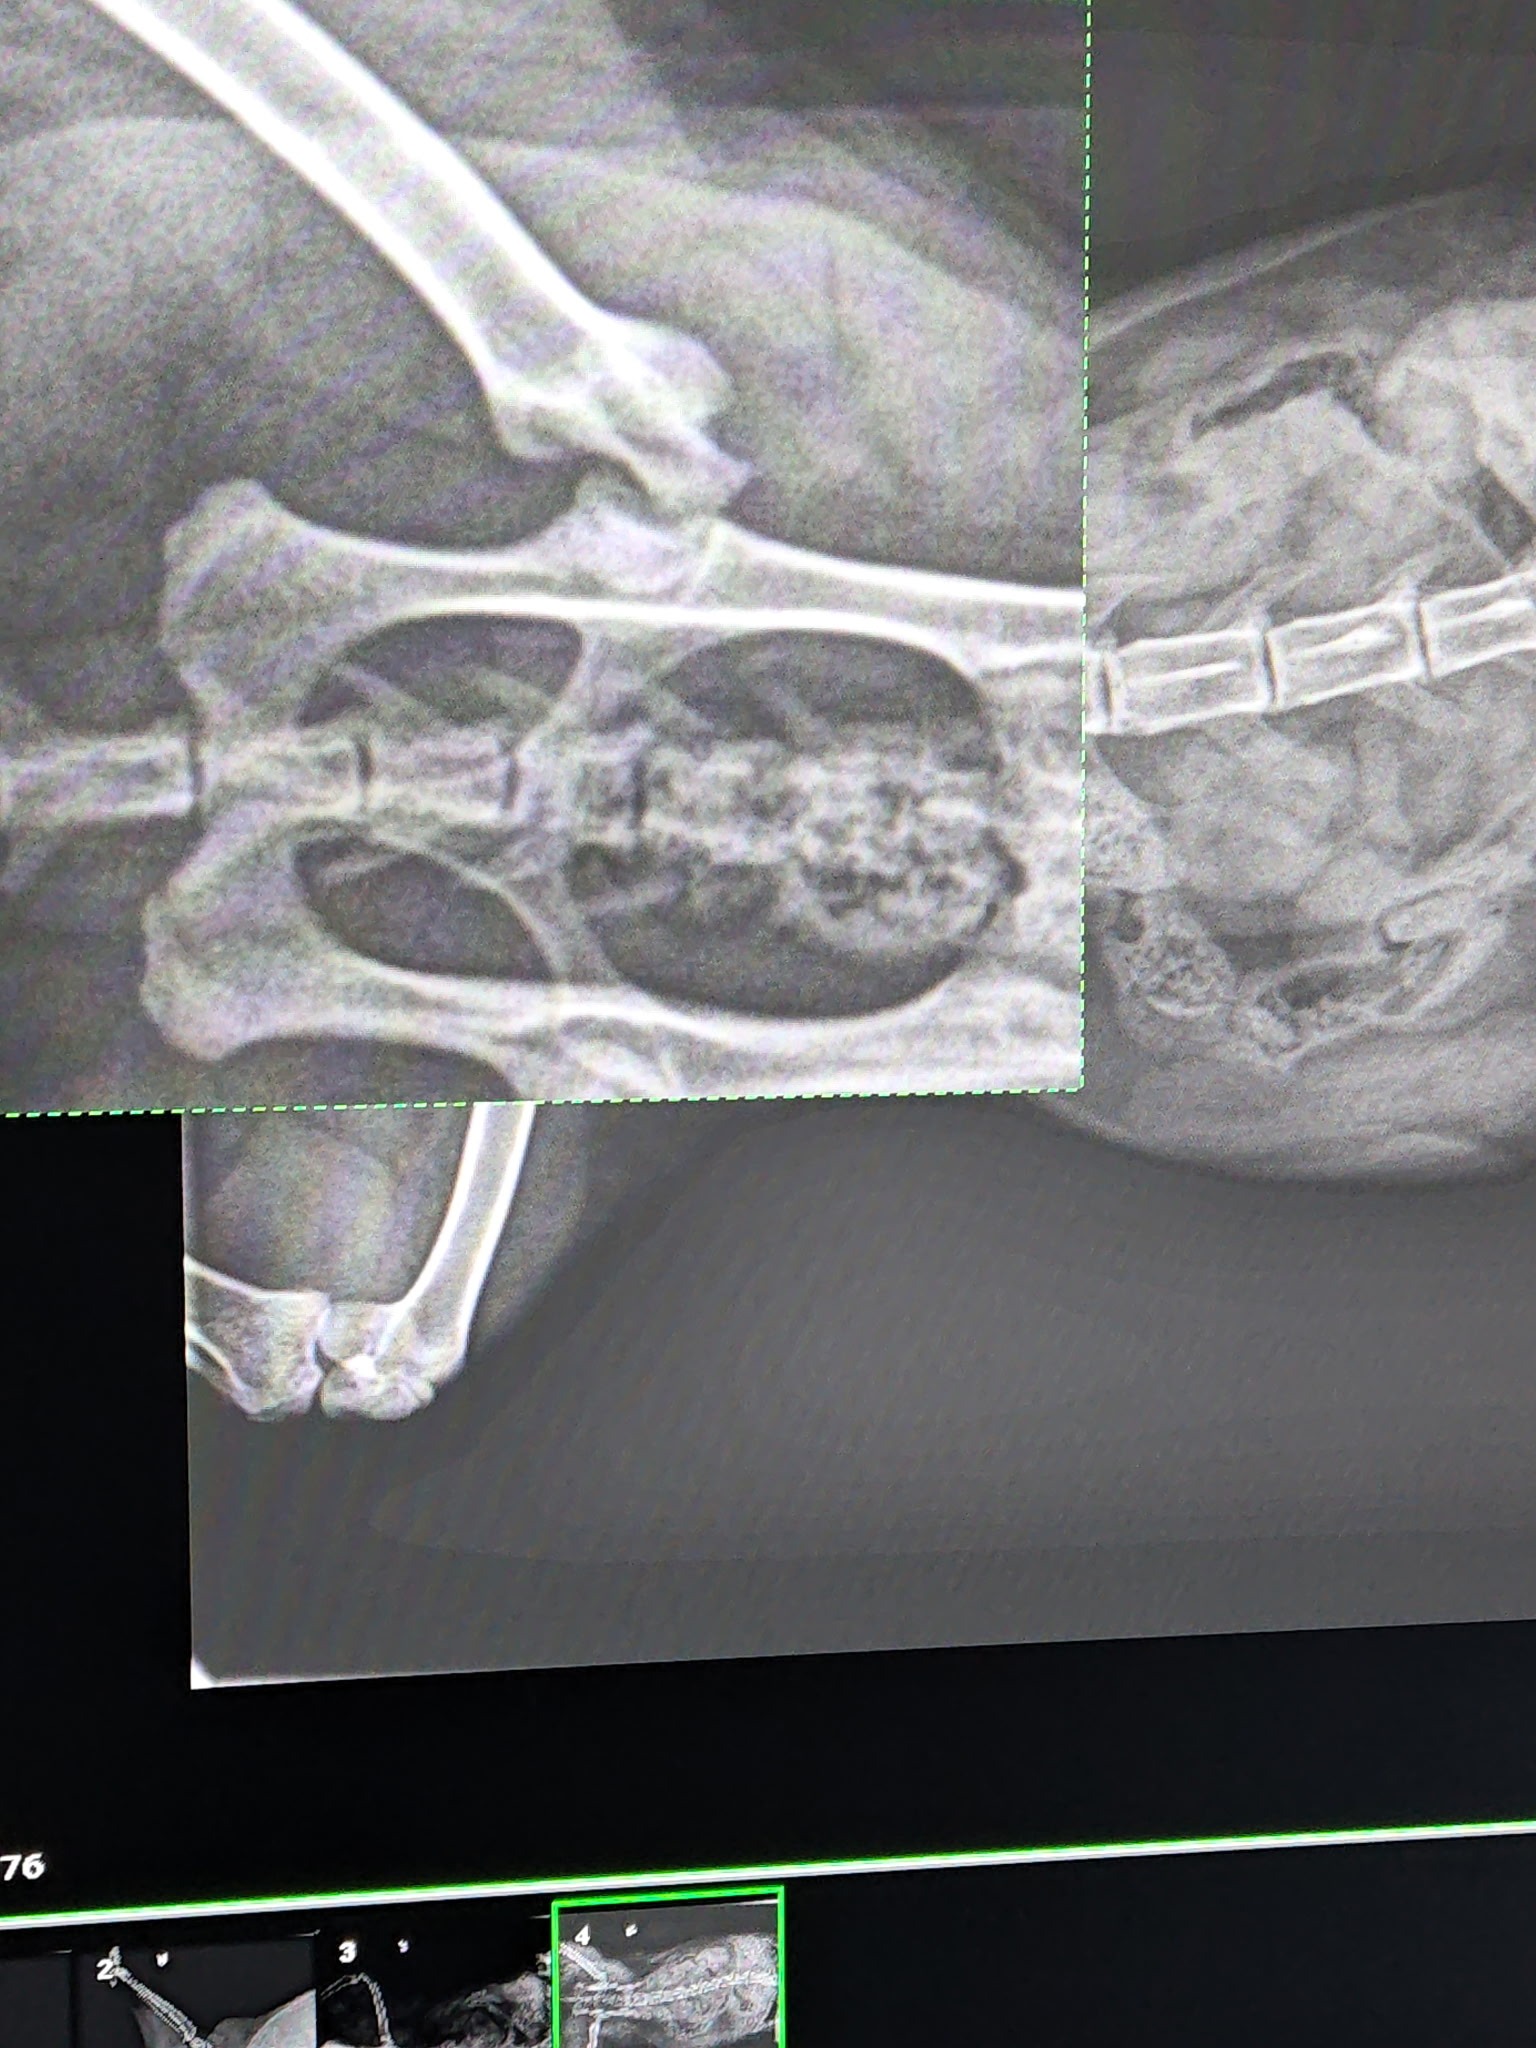

Hi. This is a first for me, but i am in a bad situation with my Ragdoll, Blaze. Blaze is not even 2 years old and he needs extensive and expensive surgery to repair his hip. The surgery needs to be done by an orthopedic surgeon. Unfortunately I did not purchase pet insurance when I bought him and now that it is a pre existing condition, all the pet insurances I looked at won't cover his surgery. Any help would be greatly appreciated. Blaze if he could tell you would appreciate it too.